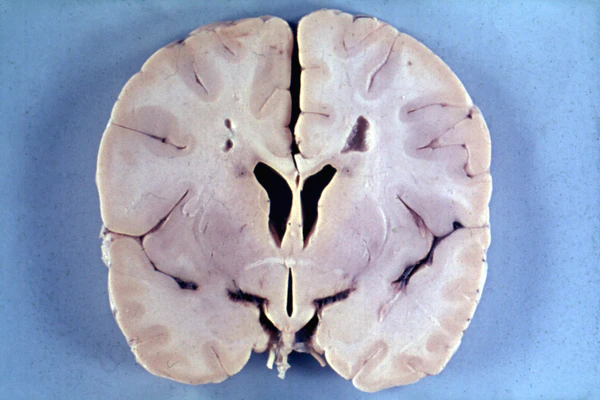

Болезнь Александера — патологоанатомически демиелинизирующая лейкодистрофия — заболевание, проявляющееся в раннем детском возрасте (до года), является наследственным[1]. Аутосомно-доминантный тип передачи. Свойственны нарушения метаболизма в астроцитах. Наблюдается задержка умственного развития, увеличение массы головного мозга, высокая температура, судорожные припадки, слабый мышечный тонус, прогрессирующая гидроцефалия, пирамидные знаки. У детей Болезнь Александера протекает катастрофически, иногда наступает смертельный исход при проявлениях спастической тетраплегии и децеребрационной ригидности. У взрослых более медленное течение заболевания, с ремиссиями и остановками. Прогрессирует заболевание быстро, рано наступает летальный исход.

При магнитно-резонансной томографии головного мозга (МРТ) при болезни Александера выявляется демиелинизация различных отделов мозга (при инфантильной и юношеской формах — преимущественно в лобных с распространением на другие области, при взрослой — более выражена в мозжечке и стволе мозга).

Подтверждением заболевания служит обнаружение волокон Розенталя (что возможно при биопсии мозга или уже после смерти при вскрытии).